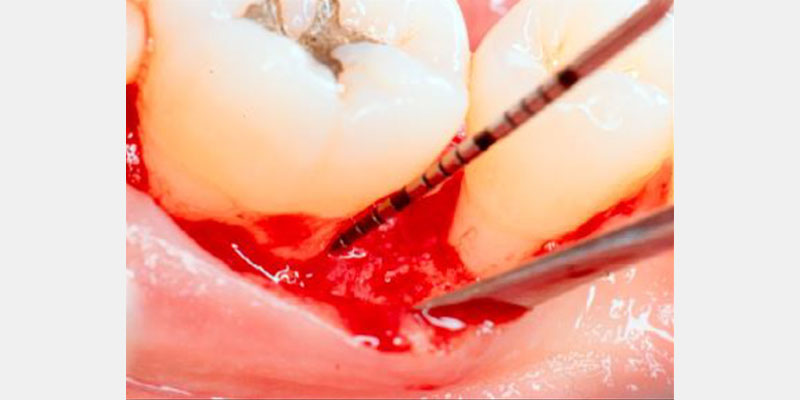

Periodontal defects include the intrabony and furcation-type defects, as well as with gingival recession or loss of attachment. The periodontal literature validates the regenerative potential of biologically active bone replacement grafts (Figs. 1–5).5, 6, 7 Periodontal regeneration with histological evidence of new cementum, periodontal ligament and alveolar bone has been shown in the human model with a recombinant growth factor and a porcine (pig)-derived protein.8, 9, 10

The ability to reconstruct the tissues in an area that was previously infected by periodontitis serves as the ultimate acid test for regenerative achievement. Human recombinant platelet-derived growth factor (PDGF-BB), a protein that regulates cell growth and division, and beta tricalcium phosphate (β-TCP), a drug delivery system for bone, have been shown to accelerate clinical attachment level gains and significantly increase bone growth in severe periodontal defects.11 Recombinant human platelet-derived growth factor (rhPDGF-BB) and enamel matrix derivative (EMD) have demonstrated tissue regeneration when used adjacent to a previously diseased root surface.8, 9, 10

Histologic evidence from a recent study shows that regeneration can be achieved with rhPDGF-BB, β-TCP, and collagen in gingival recession-type defects.12 Gingival recession defects have been treated successfully with rhPDGF, β-TCP and a collagen membrane with a root coverage technique (Figures 6–7). This technique was compared to a subepithelial connective tissue graft within a case series,13 and more recently in a controlled clinical trial. The comparisons demonstrated that the growth factor technique was comparable to the others for root coverage outcomes.14 Many studies validate the use of EMD for periodontal and mucogingival defects.5, 6, 15 The histological article on EMD offers proof of principle for incredible quantities of true periodontal regeneration.16